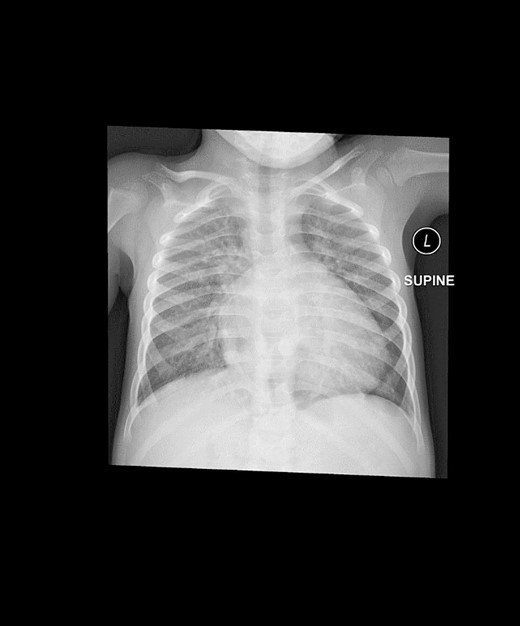

A preoperative assessment revealed an unexpected diaphragmatic hernia found incidentally on a routine chest X-ray (Fig. 1). This led to further tests, including a chest computed tomography (CT), which showed a central diaphragmatic defect with part of the transverse colon herniated into the chest (Fig. 2). Additionally, echocardiography found a perimembranous VSD with bidirectional shunting and mild tricuspid valve regurgitation. Cardiac catheterization confirmed reactive pulmonary vascular resistance.

This is a preoperative chest X-ray with an AP view revealing subtle lucent mediastinal structures in the lower mid-chest.